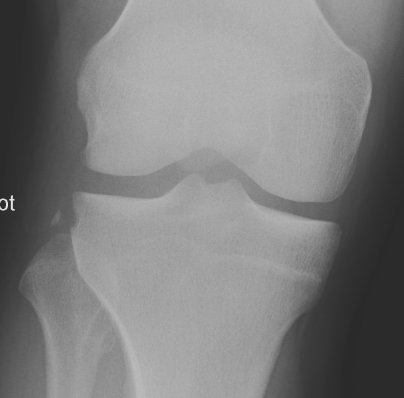

Segond Fracture

This is a very subtle "avulsion fracture of the tibia below the articular margin" caused by traction on the capsular or coronary ligaments. It is not possible to cause this fracture without first rupturing at least one of the major ligaments in the knee.

Examples in order of increasing subtlety: -